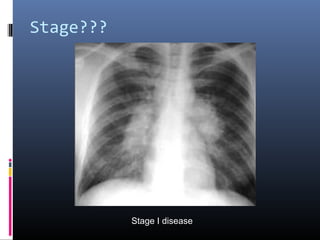

Stage???

Stage I disease

• #9 Sarcoidosis, thoracic. Stage I disease. Standard posteroanterior chest radiograph in a 28-year-old man shows extensive bilateral hilar and mediastinal lymph node enlargement not associated with a pulmonary abnormality

• #13 Stage I sarcoidosis. Posteroanterior chest radiograph demonstrates bilateral hilar and right paratracheal lymphadenopathy. Lung fields are clear.